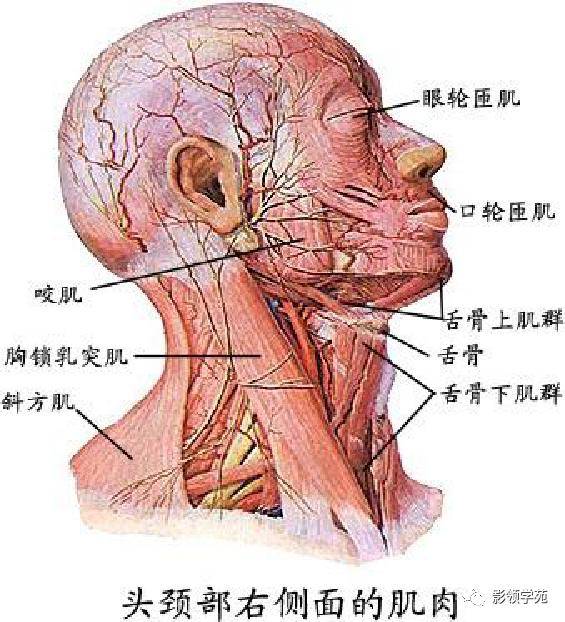

骨骼系统

骨骼系统